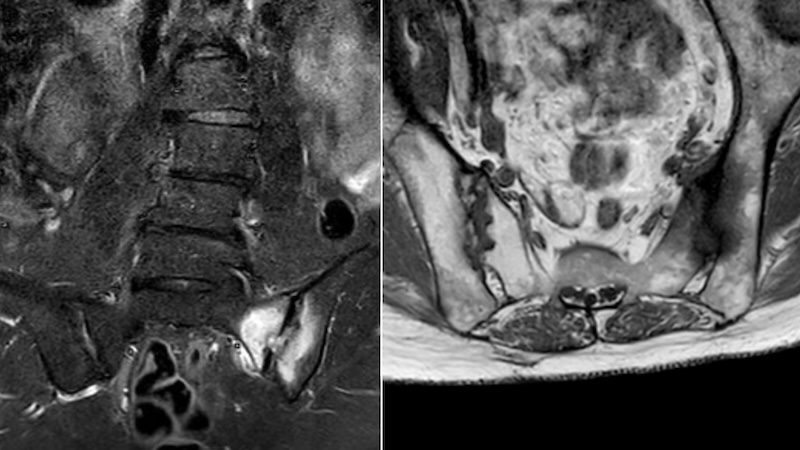

Undoubtedly, imaging – first of all, X-ray and MRI of the axial skeleton – plays an important role for the diagnostic assessment of patients with suspected axSpA and its differentiation from other conditions. A number of recent publications report a substantial variability in the interpretation of conventional radiographs and MRI, which is especially evident when local assessment is compared to a central expert’s judgment. Furthermore, an increasing number of publications cast doubt on the specificity of the "positive MRI" of sacroiliac joints, especially if MRI findings are interpreted without taking the clinical context into account.